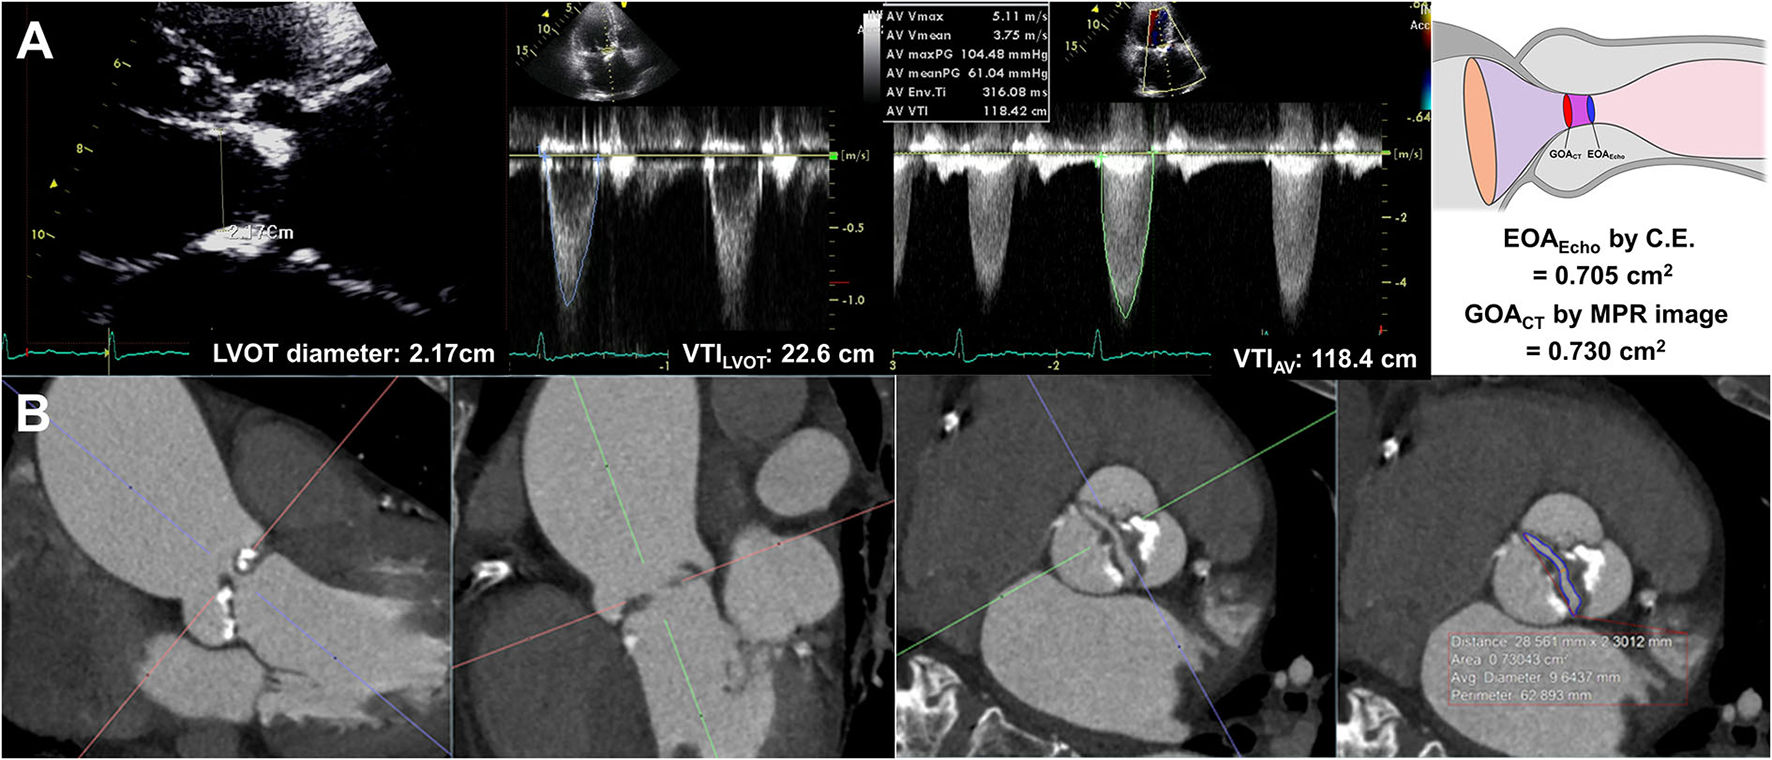

EOAEcho was derived from the continuity equation. The left ventricular outflow tract (LVOT) flow was assessed on the apical three-chamber view. The LVOT diameter was measured during mid-systole 0.5–1 cm below the aortic annulus on the parasternal long-axis view. The velocity–time integral of the LVOT (VTILVOT) was assessed using pulse-wave Doppler. Assuming the circular geometry of the LVOT, the stroke volume was calculated using the following formula: LVOT diameter2 × 0.785 × VTILVOT. The highest peak velocity across the AV, mean pressure gradient (MPG), and velocity-time integral of the AV (TVIAV) were measured from multiple windows using continuous-wave Doppler (Figure 1). All measurements represent an average of three cardiac cycles for patients with sinus rhythm and an average of five cardiac cycles for patients with atrial fibrillation. The severity of AS and combined aortic regurgitation (AR) was assessed based on the current guidelines (15, 16).

Figure 1

Effective orifice area by continuity equation (A) and geometric orifice area by multiplanar computed tomography image (B).

All CT scans were performed with a dual-source CT scanner (SOMATOM Definition Flash; Siemens Healthcare, Forchheim, Germany). Before CT angiography, a non-enhanced prospective ECG-gated scan was performed to measure aortic valve calcium score with standardized calcium scan parameters (slice collimation of 0.6 mm, slice width of 3.0 mm, tube voltage of 120 kV, and a tube current of 50 mAs). CT angiography was performed in retrospective ECG-gated data acquisition mode using the triple-phase injection method (70 ml of iopamidol followed by 30 ml of 30% blended iopamidol with saline and 20 ml of saline at 5 ml/s). Images were generated using iterative reconstruction (sinogram-affirmed iterative reconstruction). Image reconstruction was performed with a medium kernel (I36f), and the reconstruction slice thickness was 0.75 mm with 0.5–mm increments. For all patients, 10 transverse data sets were reconstructed every 10% of the cardiac cycle. Image analysis was performed using 3D software (Aquarius iNtuition, Ver. 4.4.11, TeraRecon, San Mateo, CA, USA). For planimetry, the image volume was rotated into a plane perpendicular to the LVOT and aortic root (20). LVOT imaging involved the orientation of a cross-sectional plane of the LVOT using three orthogonal planes from multiplanar reconstruction at or immediately under the lowest implantation base of the aortic cusp, and two orthogonal diameters (minimal and maximal) were measured (4). GOACT was defined as the CT planimetry-derived AV area. Planimetry of the AV area was performed at the level of the aortic leaflet tips in the mid-systolic phase, which provided the best visualization of the open aortic valve, usually at 20–30% of the R-R interval, regardless of BAV types (Figure 1, Supplementary Figure 1). Planimetry of the LVOT was performed immediately below the AV in the same phase used for the measurement of the AV area. The angle between the LVOT-AV and aorta (°) was measured during the mid-systolic phase. The AV calcium score was measured using commercial software (Aquarius iNtuition, Ver. 4.4.11, TeraRecon, San Mateo, CA, USA). Observers segmented the AV calcium score by carefully including the region of interest in the AV leaflet and annulus and excluding calcium in the adjacent sinus of Valsalva, left ventricular outflow tract, or mitral annulus, and image noise or beam hardening artifact was excluded. From the segmented ROI, the AVC volume was measured, and an AVC score was calculated using the Agatston method (21, 22). All CT analyses were independently performed by two radiologists blinded to clinical information, echocardiographic results, and CT analysis results of the other reader. Intraclass correlation coefficients (ICCs) were calculated to assess the inter- and intra-observer variability of the GOACT. A total of 20 samples were assessed by the same observer on different occasions in random order and were also assessed by another observer.